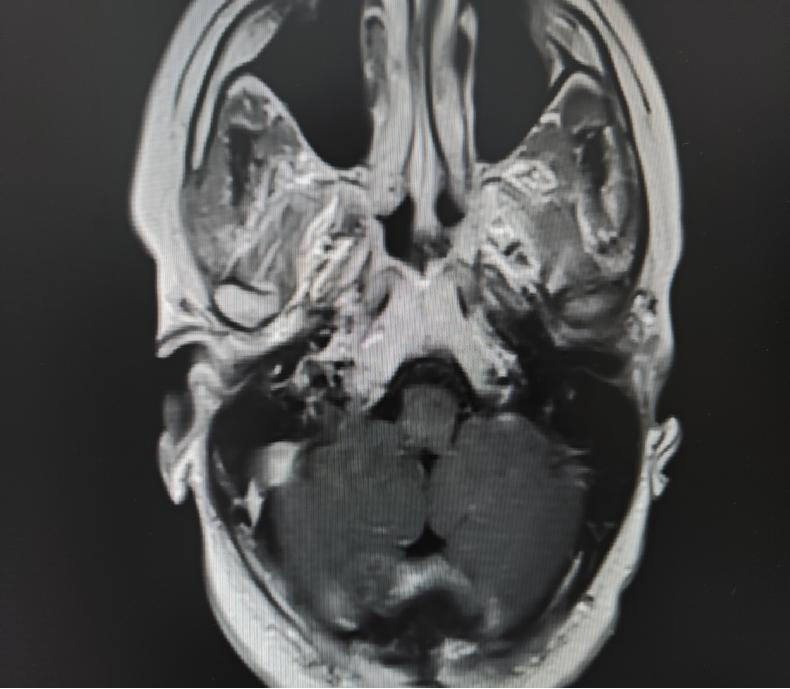

術(shù)后影像

參與手術(shù)的神經(jīng)外科大科副主任文世宏主任醫(yī)師表示,手術(shù)是在目前世界上先進的蔡氏KV900顯微鏡下完成的,操作相當(dāng)精細,用“雕刻”一詞也不為過。因為病灶位于延髓,稍有不慎,就會影響呼吸和心跳,嚴(yán)重時,可能導(dǎo)致患者術(shù)中或術(shù)后呼吸心跳停止。此次手術(shù)相當(dāng)順利,術(shù)后患者呼吸功能、吞咽功能、肢體感覺功能還是有一定影響,經(jīng)過李毅毅主任醫(yī)師帶領(lǐng)的神經(jīng)重癥團隊的精細化治療,呼吸機輔助治療一段時間后逐漸脫機;經(jīng)康復(fù)科早期介入,進行了針灸、理療等功能訓(xùn)練,患者慢慢恢復(fù)正常進食,肢體麻木逐漸好轉(zhuǎn),家屬及患者都非常開心。

手術(shù)是在神經(jīng)電生理的密切監(jiān)測下完成的,實現(xiàn)術(shù)中持續(xù)評估神經(jīng)通路的功能完整性,對于解剖上難以確定的神經(jīng)組織進行功能鑒定和保護,減少了術(shù)中及術(shù)后可能出現(xiàn)的神經(jīng)功能損害,大大增加了手術(shù)操作的精準(zhǔn)性和安全性,最大程度避免損傷神經(jīng)功能?;颊吣茼樌鲈?,安返家庭和工作崗位,神經(jīng)電生理監(jiān)測組也是功不可沒!